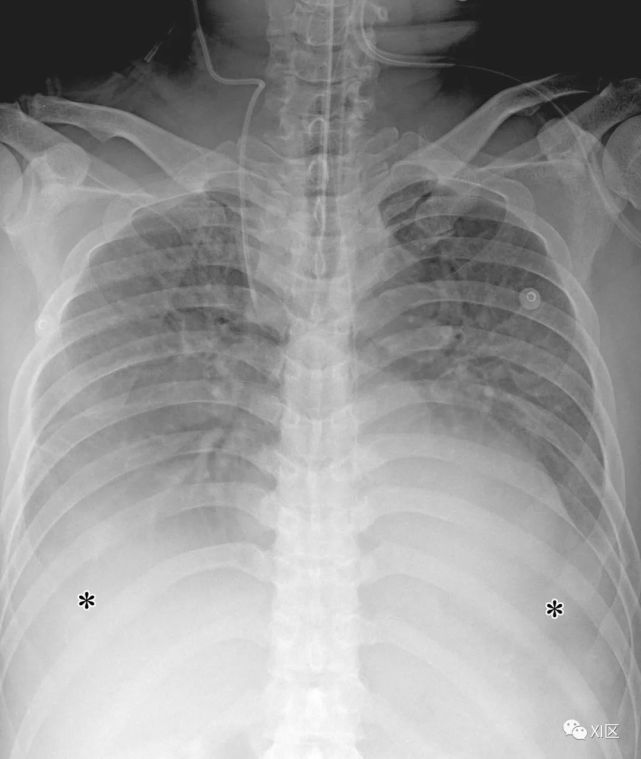

汉坦病毒心肺综合征特征性累及肺,表现为非心源性水肿引起的呼吸窘迫。经过17-42天的潜伏期后,临床阶段开始于前驱期,并继续到呼吸衰竭和恢复期。临床症状包括干咳和呼吸困难。放射学表现最初通常是正常的,或包含最小的间质水肿。胸腔积液很常见。肺间质性水肿可能很严重,尽管通常是短暂的。一些病历表现为,48小时内迅速发展双肺含气腔隙性实变和暴发性呼吸恶化。这些肺部表现偶尔继发于肾功能衰竭。

图19 52岁男性,汉坦病毒感染,因发烧及急性肾功能衰竭就诊。最初的胸部CT表现正常(未显示)。患者在就诊后1天,突然血压下降,胸片显示肺水肿和双侧胸腔积液(*)。汉坦病毒抗体检测结果为阳性,滴度提高到1:512。进行了强化治疗,病人康复。

Koo H J , Lim S , Choe J , et al. Radiographic and CT Features of Viral Pneumonia[J]. Radiographics, 2018, 38(3):719-739.